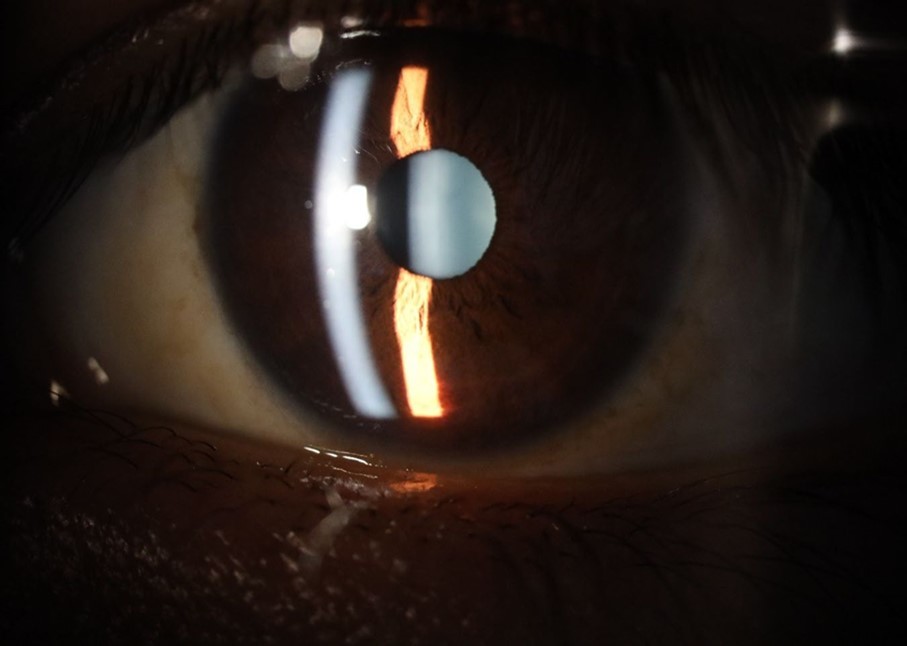

Figure 25.Mirror reflection of the affected eye (right side), with good appearance. This indicates that the transparent media of the eyeball (Cornea, anterior chamber, lens, and vitreous) are in good condition.

Figure 26.The macrograph of the anterior segment of the right eye (affected) shows very good transparency of the cornea, anterior chamber, lens, and vitreous.

Figure 31.The photograph of the right eye shows an almost normal mirror reflection, as well as a better pupillary dilation.

Figure 32.The macro photograph of the right eye shows us a cornea, anterior camera, and crystalline lens in very good condition.